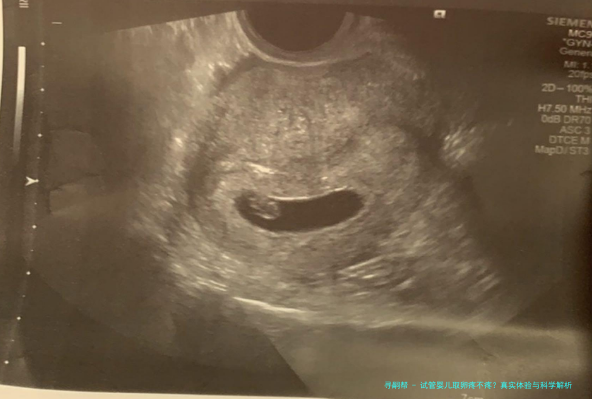

说到身体感受,取卵过程通常是在B超引导下进行的,医生会用一根细针通过阴道穿刺到卵巢,把成熟的卵子吸出来。这听起来可能有点吓人,但实际上,很多女性反馈感觉更像是月经来时的轻微胀痛或痉挛,持续时间很短,也就几分钟的事儿。当然,也有姐妹说几乎没感觉,睡一觉就完成了。疼痛程度跟个人体质、卵泡数量有关,比如卵泡多的话,可能胀感明显些,但一般不会剧痛到无法忍受。我自己听医生朋友讲,大多数患者术后都说:“哎呀,比预想的轻松多了!”这种反馈挺常见的。